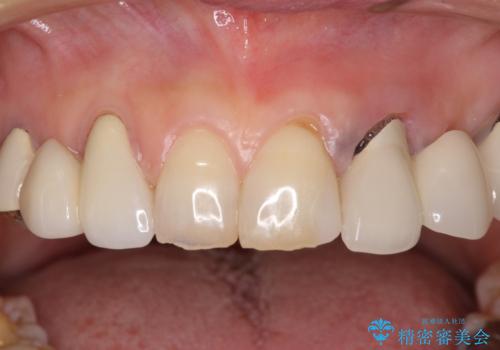

- 割れていると言われて放置してしまった歯や、前歯のデコボコなどが気になるとのことで来院された患者様です。

左上の歯は割れてしまっており、抜歯のうえインプラント治療が必要であり、他にも抜歯の必要な歯がある状態でした。